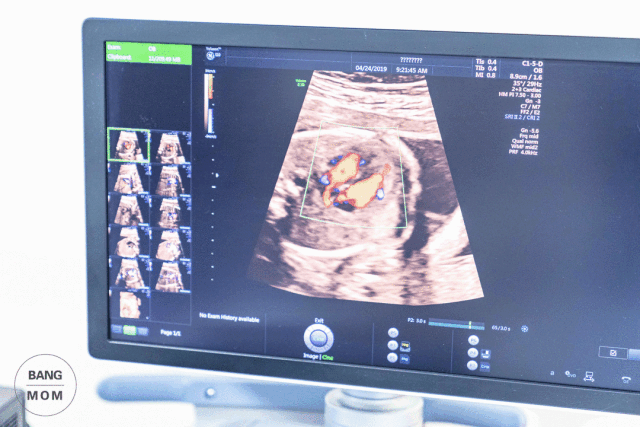

超声检查是在孕期给宝宝办理“健康证”。四维彩超、B超是产检排除畸形的重要环节。在同安坐镇的首席超声专家是吕慧玲。她曾任青岛妇儿中心特检科主任,市立医院东院产科超声室主任。

多年的工作经验,让她练就一双火眼金睛,根据手中的探头和仪器,就能观察到胎儿的样子和健康状况。甚至连3厘米大的心脏,其内部结构和血流方向,都看得清楚。

同安的四维彩超是预约制,为了保证孕妈的检查时间和就诊的舒适度,每天只开放10个预约名额。

使用的仪器是美国GE-E10高清四维彩超仪。这一型号的仪器,堪称彩超界的战斗机,画面清晰的程度,不止一点点。